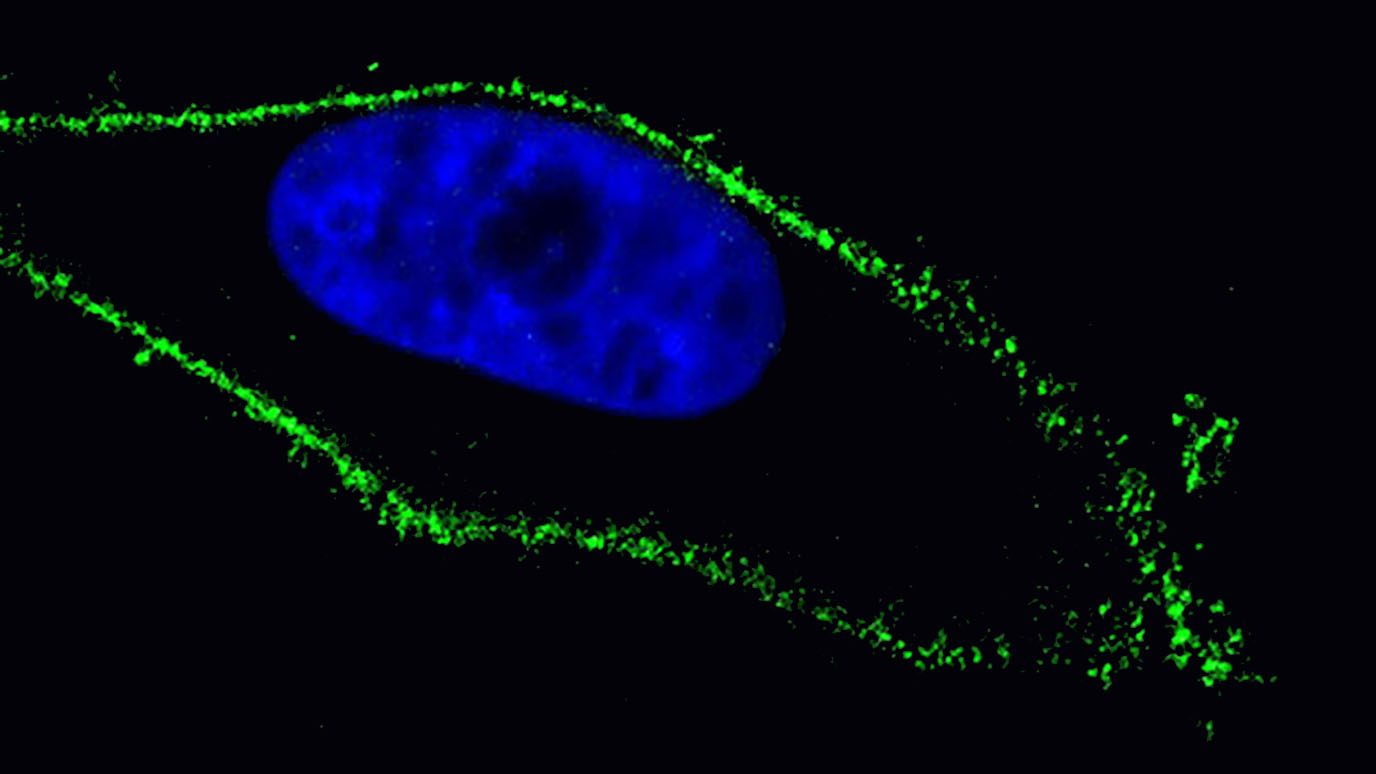

AACR: Single-cell study uncovers distinct immunosuppressive tumor microenvironment in brain metastases from kidney cancer

In a new study, researchers from The University of Texas MD Anderson Cancer Center created the largest single-cell atlas...